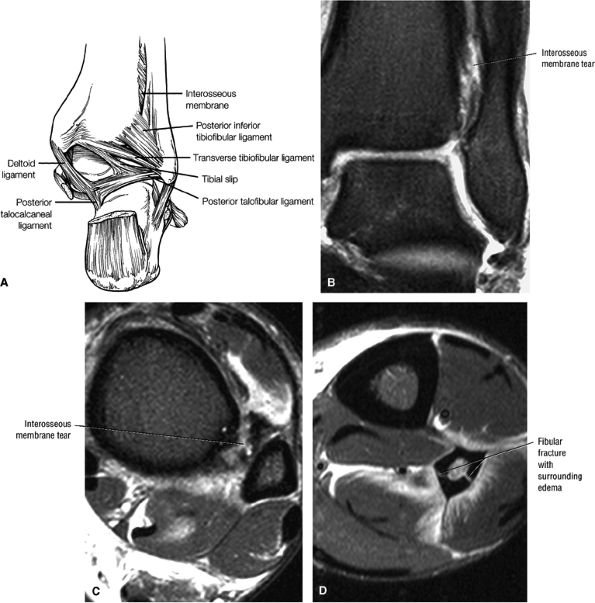

The syndesmotic ligaments consist of the anterior syndesmotic or anterior inferior tibiofibular ligament and the posterior syndesmotic or posterior inferior tibiofibular ligament, the interosseous membrane, and the transverse tibiofibular ligament.

The transverse tibiofibular ligament represents the posterior labrum of the ankle and projects inferior to the posterior tibial margin.

The tibial slip is the posterior intermalleolar ligament.